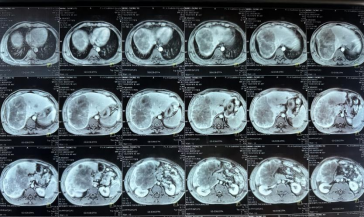

影像学检查:2024年7月30日,院外腹部CT显示乙状结肠管壁增厚,考虑肿瘤性病变(cT3N2,图1),2024年8月5日,肝脏MRI显示肝脏多发转移灶(侵犯门静脉右支、肝右静脉,图2)。2024年8月2日胸部CT显示双肺结节待排(图3)。

图2. 肝脏MRI